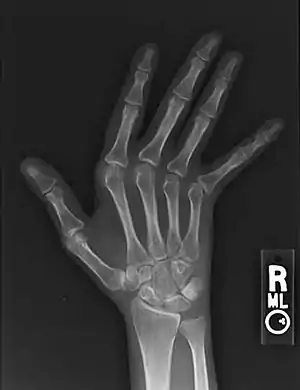

| Jaccoud arthropathy seen on a hand x-ray. As opposed to arthropathy due to rheumatoid arthritis, there are no erosions. | |

Plain hand radiographs typically show marked ulnar subluxation and deviation at the metacarpophalangeal joints. Absence of erosions is a notable feature, although occasionally "hook" erosions may be observed, which are similar to those seen in SLE and ankylosing spondylitis. Evidence of muscle (soft tissue) atrophy also may be present.